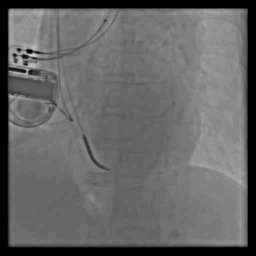

病例七

病例八

术前冠脉造影

血管选择 一

血管选择二

血管选择三

术中测试

● 左心室阈值:LV4-Coil 1.25V

● 右心室阈值:0.5V

● 右心房阈值:0.5V

最终影像